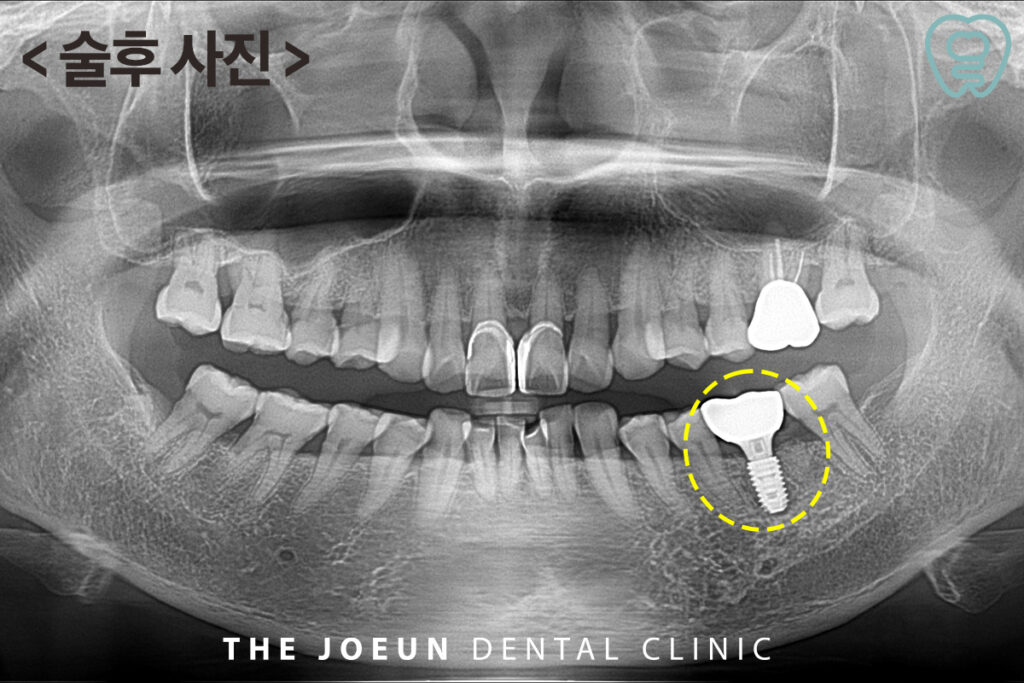

약 4개월 뒤, 잇몸뼈와 인공치근의 고정력을 확인한 뒤 최종 보철물을 완성하였습니다.